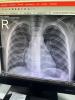

Симптомы пневмонии у детей: как распознать и что делать

Девочки кто понимает,есть пневмония ?